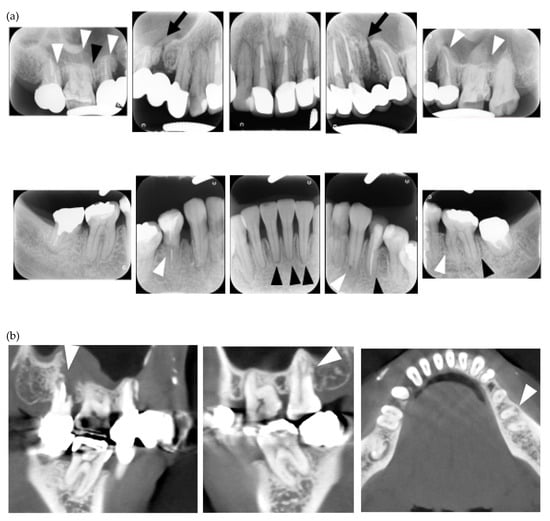

Figure 2.

Multiple external root resorption and calcinosis at the oral region in pt. 3. A dental X-ray photo and CBCT image of teeth (a,b) and the deposition of calcinosis at the nasal spur (c). The white arrowhead points to root resorption, the black arrowhead to PDL space widening, the white arrow at calcinosis and the black arrow indicates the failure to close the space with orthodontic treatment.

In the present study, MERR was detected in four SSc patients, including one described in a case report (pt. 1) [12]. The causes of external resorption, including trauma, periodontal and periapical inflammation, orthodontic treatment, internal bleaching or tumors, were not found in the teeth having external resorption. Dental X-rays and CBCT images showed that MERR was observed in six, six, and four teeth in pts. 2, 3, and 4, respectively (Figure 1a, Figure 2a and Figure 3a). A widening PDL space was detected in all patients. A space between canines and premolars in the upper jaw was found in pts. 3 and 4 (Figure 2a and Figure 3a). Furthermore, the deposition of calcinosis in the nasal spur was noted in pts. 1, [12], 2, and 3, while calcinosis in the palatal plate was observed in pt. 4 (Figure 2c and Figure 3c).